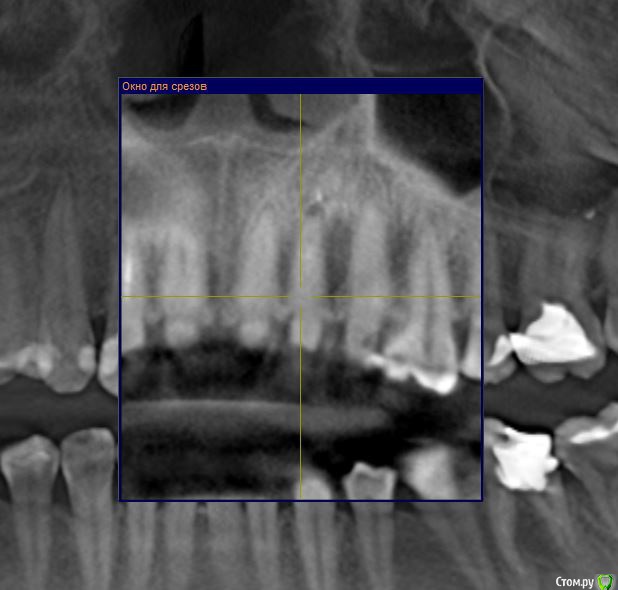

Gusenica Опубликовано 29 января, 2017 Поделиться Опубликовано 29 января, 2017 (изменено) Добрый день, уважаемые стоматологи! Прошу вас подтвердить правильность действия моих стоматологов. В частности интересует, безнадежен ли мой 36 зуб, на нем 2 кисты и я так и не поняла, почему их нельзя вылечить, но мой врач категорично настаивает на удалении. Зуб разрушен, имеет розово-серый цвет, лечился когда-то резорцином. На втором снимке киста на 22 зубе была обнаружена врачем уже после эстетического лечения, на ортопантомограмме она ее не увидела. А перелечивать мне не захотелось, при том она не настаивала, мол можно просто ее наблюдать, что она маленькая и неопасная. Так ли это? Может все же нужно лечить? И последний вопрос: зуб 46 -каналы пломбировались резорцином и сильно склерозированы. После консультации с ортопедом решили их не перелечивать, а сразу ставить на него коронку. Как вы считаете это правильное решение? Не появится ли там киста в итоге? Добавлю, что зубы с кистами никогда не беспокоили. Буду признательна за консультацию. Изменено 29 января, 2017 пользователем Gusenica Ссылка на комментарий

Доктор Добрых Дел Опубликовано 29 января, 2017 Поделиться Опубликовано 29 января, 2017 (изменено) Зуб 36 помимо кист (а точнее гранулём) имеет патологическую резорбцию корней в апикальной части поэтому перелечить его невозможно. Зуб 22 можно и наблюдать конечно, но канал недопломбирован, поэтому лучше перелечить. Зуб 46 кандидат на удаление так как судя по снимку разрушение копонковой части зуба потребует изготовления культевой вкладки, а так как каналы склерозированы их придётся рассверливать, а так как зуб резорциненый и хрупкий как стекло в будущем это с высокой ддолей вероятности приведёт к перелому корня. Я бы рекомендовал удаление 36, 46 и установку имплантатов. Перелечтвание 22. Прошу учесть, что рекомендации не являются руководством к действию. Решение принимать Вам и Вашему лечащему врачу. Изменено 29 января, 2017 пользователем Доктор Добрых Дел 1 Ссылка на комментарий